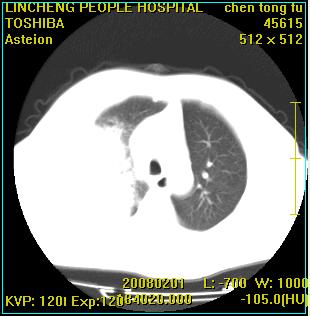

标题: CT11942:男性,62岁。右肺的病变 [打印本页]

患者,男性,62岁。主因头晕,发热,咳嗽6天,高热达39度,esr19mm/h,wbc 3.9×10 9/l

实变区见空气支气管征,支气管通畅,考虑为大叶性肺炎,右侧少量胸水

实变区见空气支气管征,支气管通畅,考虑为大叶性肺炎,右侧少量胸水。